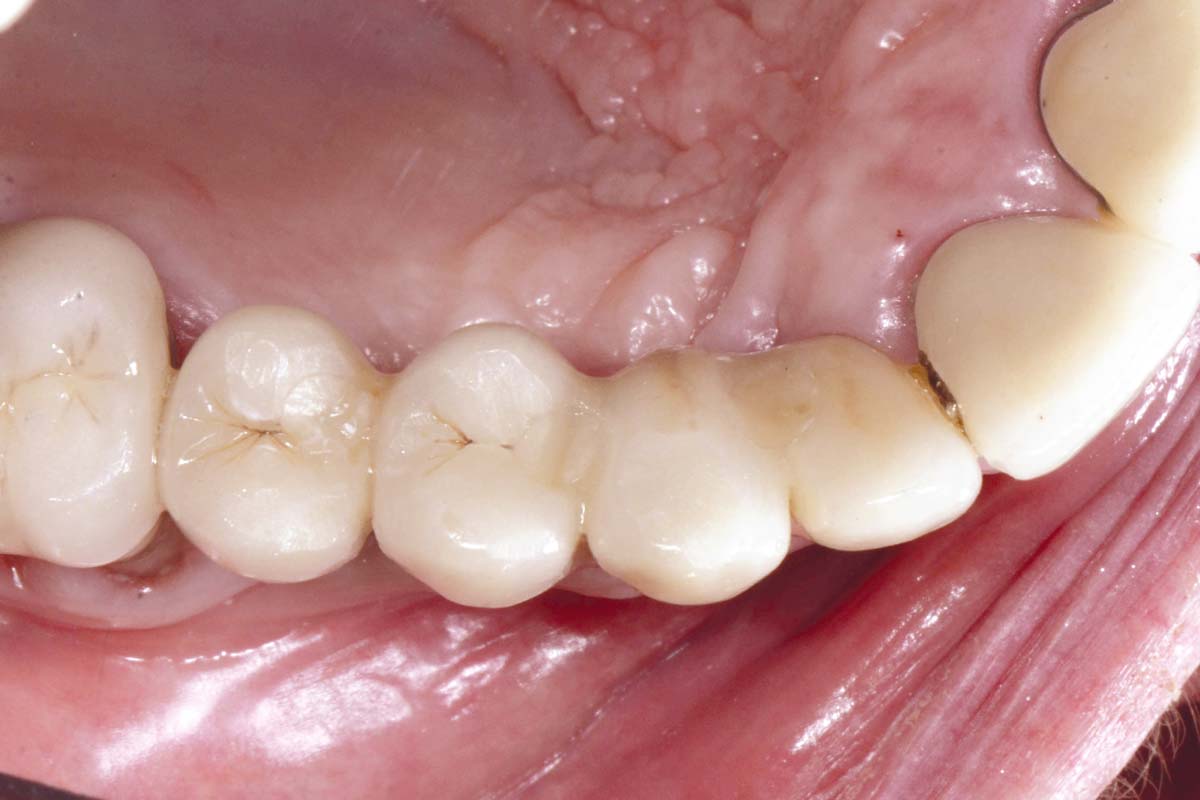

Ridge augmentation with maxgraft® bonebuilder and sinus floor elevation – Dr. K.P. Schiechl

Initial clinical situation: Bone defect in the upper right maxilla (teeth #14-16)